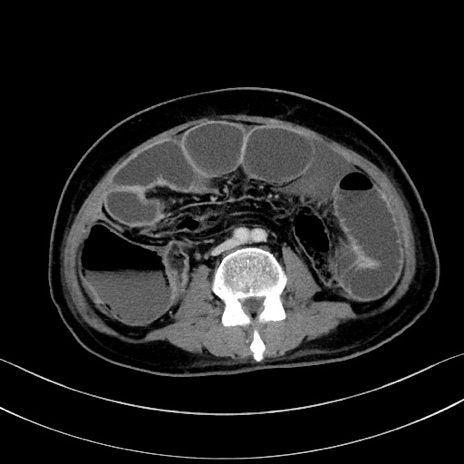

症例28(横断像)

【症例】60歳代男性

【主訴】嘔吐

【現病歴】胃癌にて胃全摘後。食思不振が悪化し、夜中に嘔吐することがある。

【既往歴】胃癌、胃全摘、脾摘、胆摘後

【データ】WBC 5900、CRP 10.56